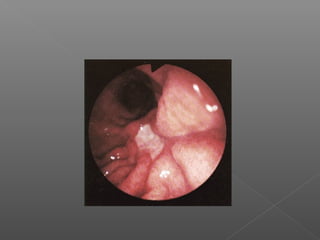

Dieulafoy

Argón

Angiodisplasia

Heater probe

II. Métodos térmicos

Se basan en la aplicación de calor para el logro de la hemostasia.

No contacto

Laser

Argón plasma